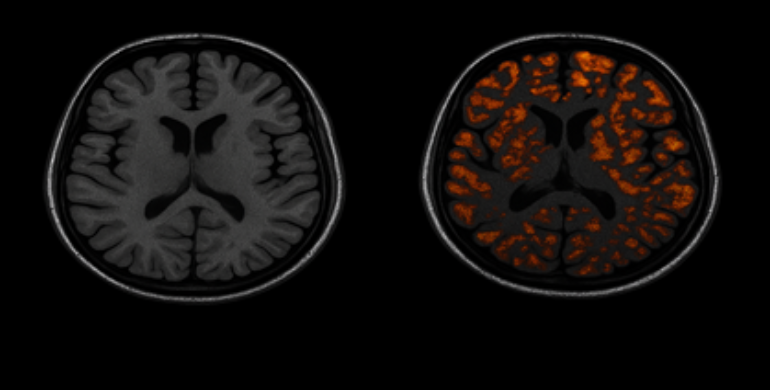

There was a short article about anosmia – loss of smell – as an early indicator of Alzheimer’s disease. Nothing unusual there, until I noticed the image they used: what appeared to be a generic stock image of a brain scan showing amyloid beta plaques, with no reference or explanation in the article. That struck me as strange.

Two brain MRI scans: left shows normal anatomy, right highlights orange regions indicating areas of interest.

So, when I see popular science articles today throwing around images of plaques like it's settled science… I can't help but wonder: Why are we still so attached to this hypothesis? Why can’t we see beyond the wood dust?